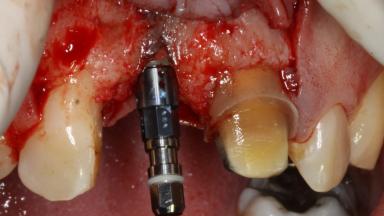

The patient presented with a failing tooth-supported fixed dental prosthesis with cantilever extension replacing the right maxillary central incisor. His chief presenting complaint was poor esthetics, in particular the dark discolored margin around the abutment tooth, the maxillary left central incisor. He reported a history of trauma at a young age, which necessitated the replacement of his maxillary right central incisor as well as root canal therapy of the adjacent left central incisor. The existing prosthesis had been in situ for over 20 years. The initial periapical radiograph displayed good proximal bone levels at the adjacent teeth and a wide incisive canal, which was a concern. The left central incisor presented a very wide root canal treatment with compromised radicular dentin thickness, which was a consideration in the decision between a new tooth-supported fixed dental prosthesis vs. an implant-supported prosthesis. After a lengthy discussion on the risks and benefits of both treatment options, the patient decided on a single-tooth implant replacement.

Bone Augmentation Simultaneous

Augmentation Materials Xenogenous